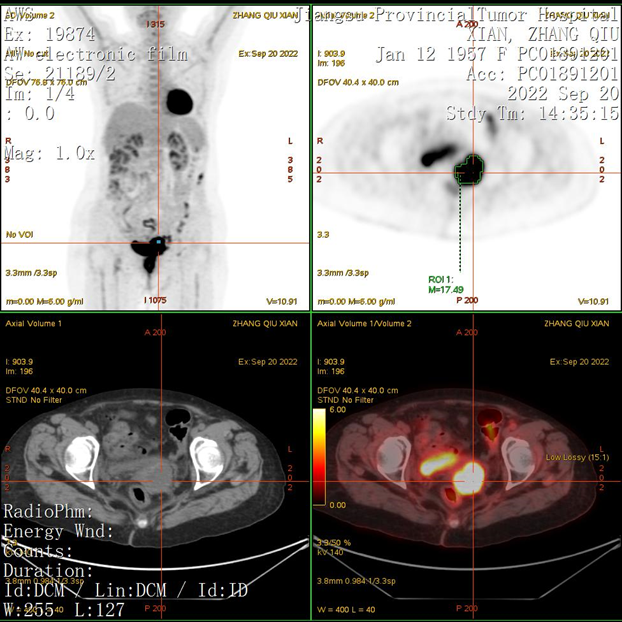

PET-CT检查:阴道全程壁增厚,FDG代谢增高,病灶累及宫颈,与直肠及膀胱前壁分界不清,考虑肿瘤复发可能大,病灶侵犯直肠及膀胱可能。

图4. PET-CT提示阴道后壁肿瘤复发,SUV值高,病灶与直肠及膀胱前壁分界不清,考虑病灶侵犯直肠及膀胱可能,另有可疑转移灶